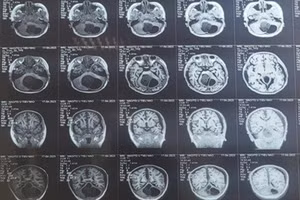

Cứu sống bệnh nhi bị u tiểu não kích thước lớn 12/05/2023 15:34 GD&TĐ - Bệnh viện Nhi Thanh Hóa phẫu thuật thành công cho bệnh nhi 10 tuổi, bị u tiểu não kích thước lớn.